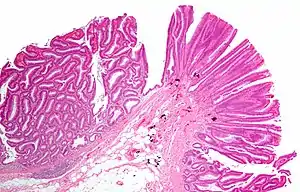

| Tubulovillous adenoma (tubular component – left of image, villous component – right of image). H&E stain. | |

Tubulovillous adenoma

Tubulovillous adenoma, TVA are considered to have a higher risk of becoming malignant (cancerous) than tubular adenomas.[9]